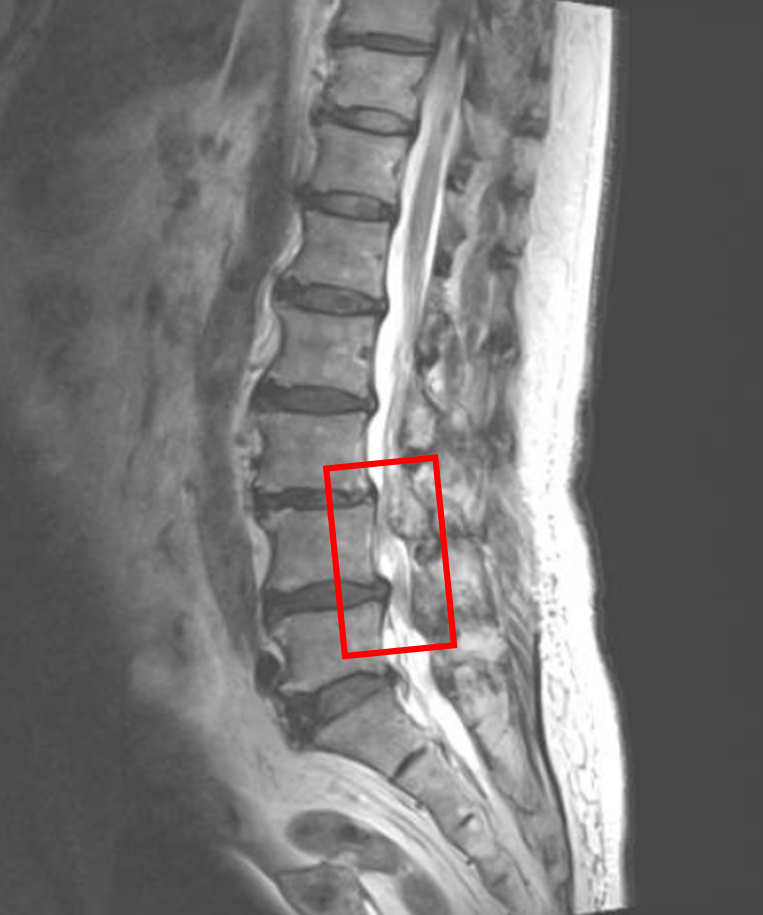

この患者様は赤い枠で示されている箇所(L3/4,4/5)に脊柱管狭窄症を認めます。